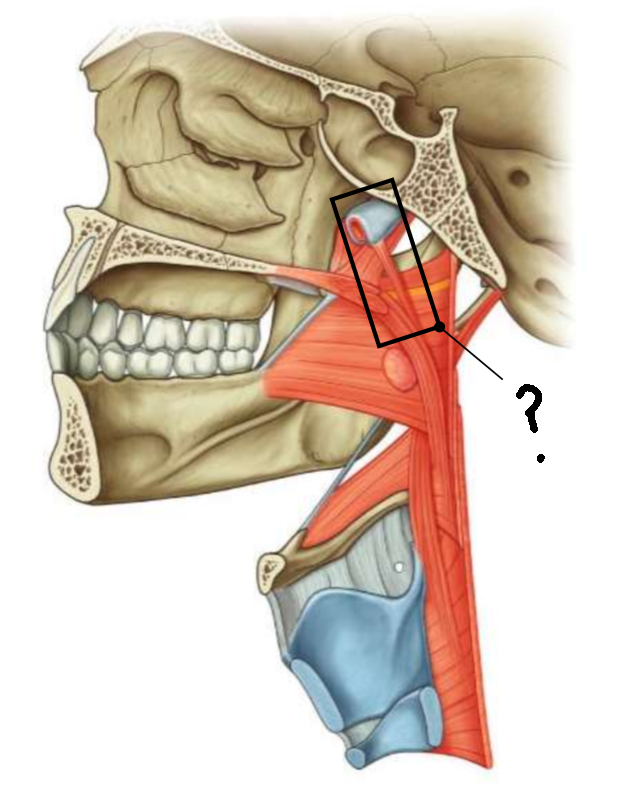

What muscle is this?

inferior constrictor

Which part of the muscle is 1?

thyropharyngeus

Which part of the muscle is 2?

cricopharyngeus

What are the attachments of this muscle?

oblique line of thyroid cartilage, cricothyroid tendon, cricoid cartilage → pharyngeal raphe

What is in the rectangle?

pharyngeal raphe

What is in the circle?

killians dehiscence

What is in the rectangle?

pterygomandibular raphe